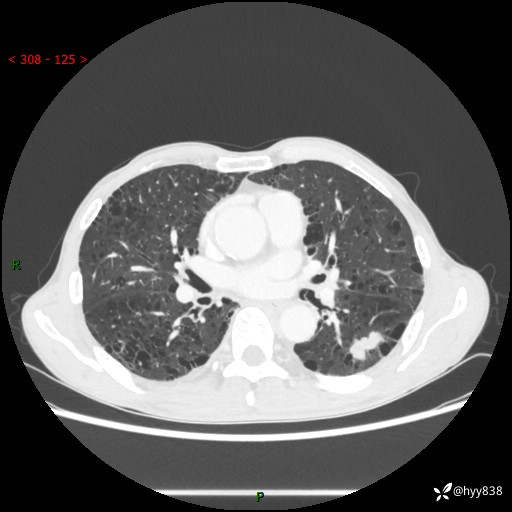

73岁/男,发现肺占位1月余。肺气肿背景,是否恶性倾向---结果公布~

现病史:患者于1月余前无明显诱因出现背部疼痛不适,无明显咳嗽、咳痰、胸闷、咯血、发热等不适,后于2024.5.3至当地市人民医院行胸部CT示:左肺下叶结块,大小约2.2cm*2.6cm,双肺多发小结节,双肺感染性病变,部分纤维增值灶,慢支并双肺局限性肺气肿,肺大泡,纵隔淋巴结增大并部分钙化,冠脉区及大血管壁钙化,双侧胸膜局限性增厚;后口服莫西沙星2周。2024.6.12复查胸部CT示:左肺下叶结块影形态较前饱满,较大截面范围约2.8cm*2.3cm,边缘可见细短毛刺及分叶,性质待查。现患者为求进一步诊治来我院,门诊以“肺占位”收入我科。 起病来,患者精神、食欲、睡眠尚可,大小便正常,体力体重轻微下降。

胸部CT平扫+增强

各期CT值:48hu 100hu 78hu